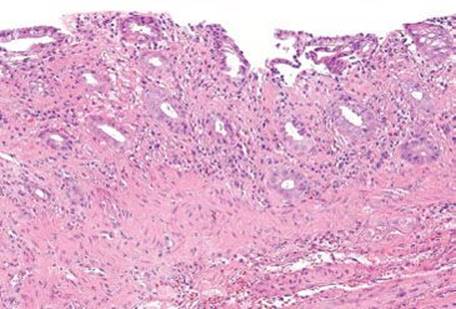

Figure 4.50 Ischemic colitis pattern. This example shows small and withered crypts near the surface. The surface epithelium has sloughed off in some areas, and lamina propria hemorrhage and hyalinization are present.

Mucosal ischemia causes a highly characteristic pattern of injury, including features of surface injury, loss of mucin, lamina propria hemorrhage and hyalinization, withered crypts, atrophic microcrypts, and lamina propria collapse (Fig. 4.50). The architectural pattern of withered crypts and microcrypts is distinctive at low magnification, and one might even refer to this pattern of injury as the “microcrypt pattern” (Fig. 4.51). Although ischemic injury is top among the differential diagnoses, other considerations include vascular injury (such as that seen in radiation colitis, amyloidosis, or vasculitis), infection (particularly Escherichia coli 0157:H7 and Clostridium difficile), and medications (NSAIDs, Kayexalate, and sevelamer).